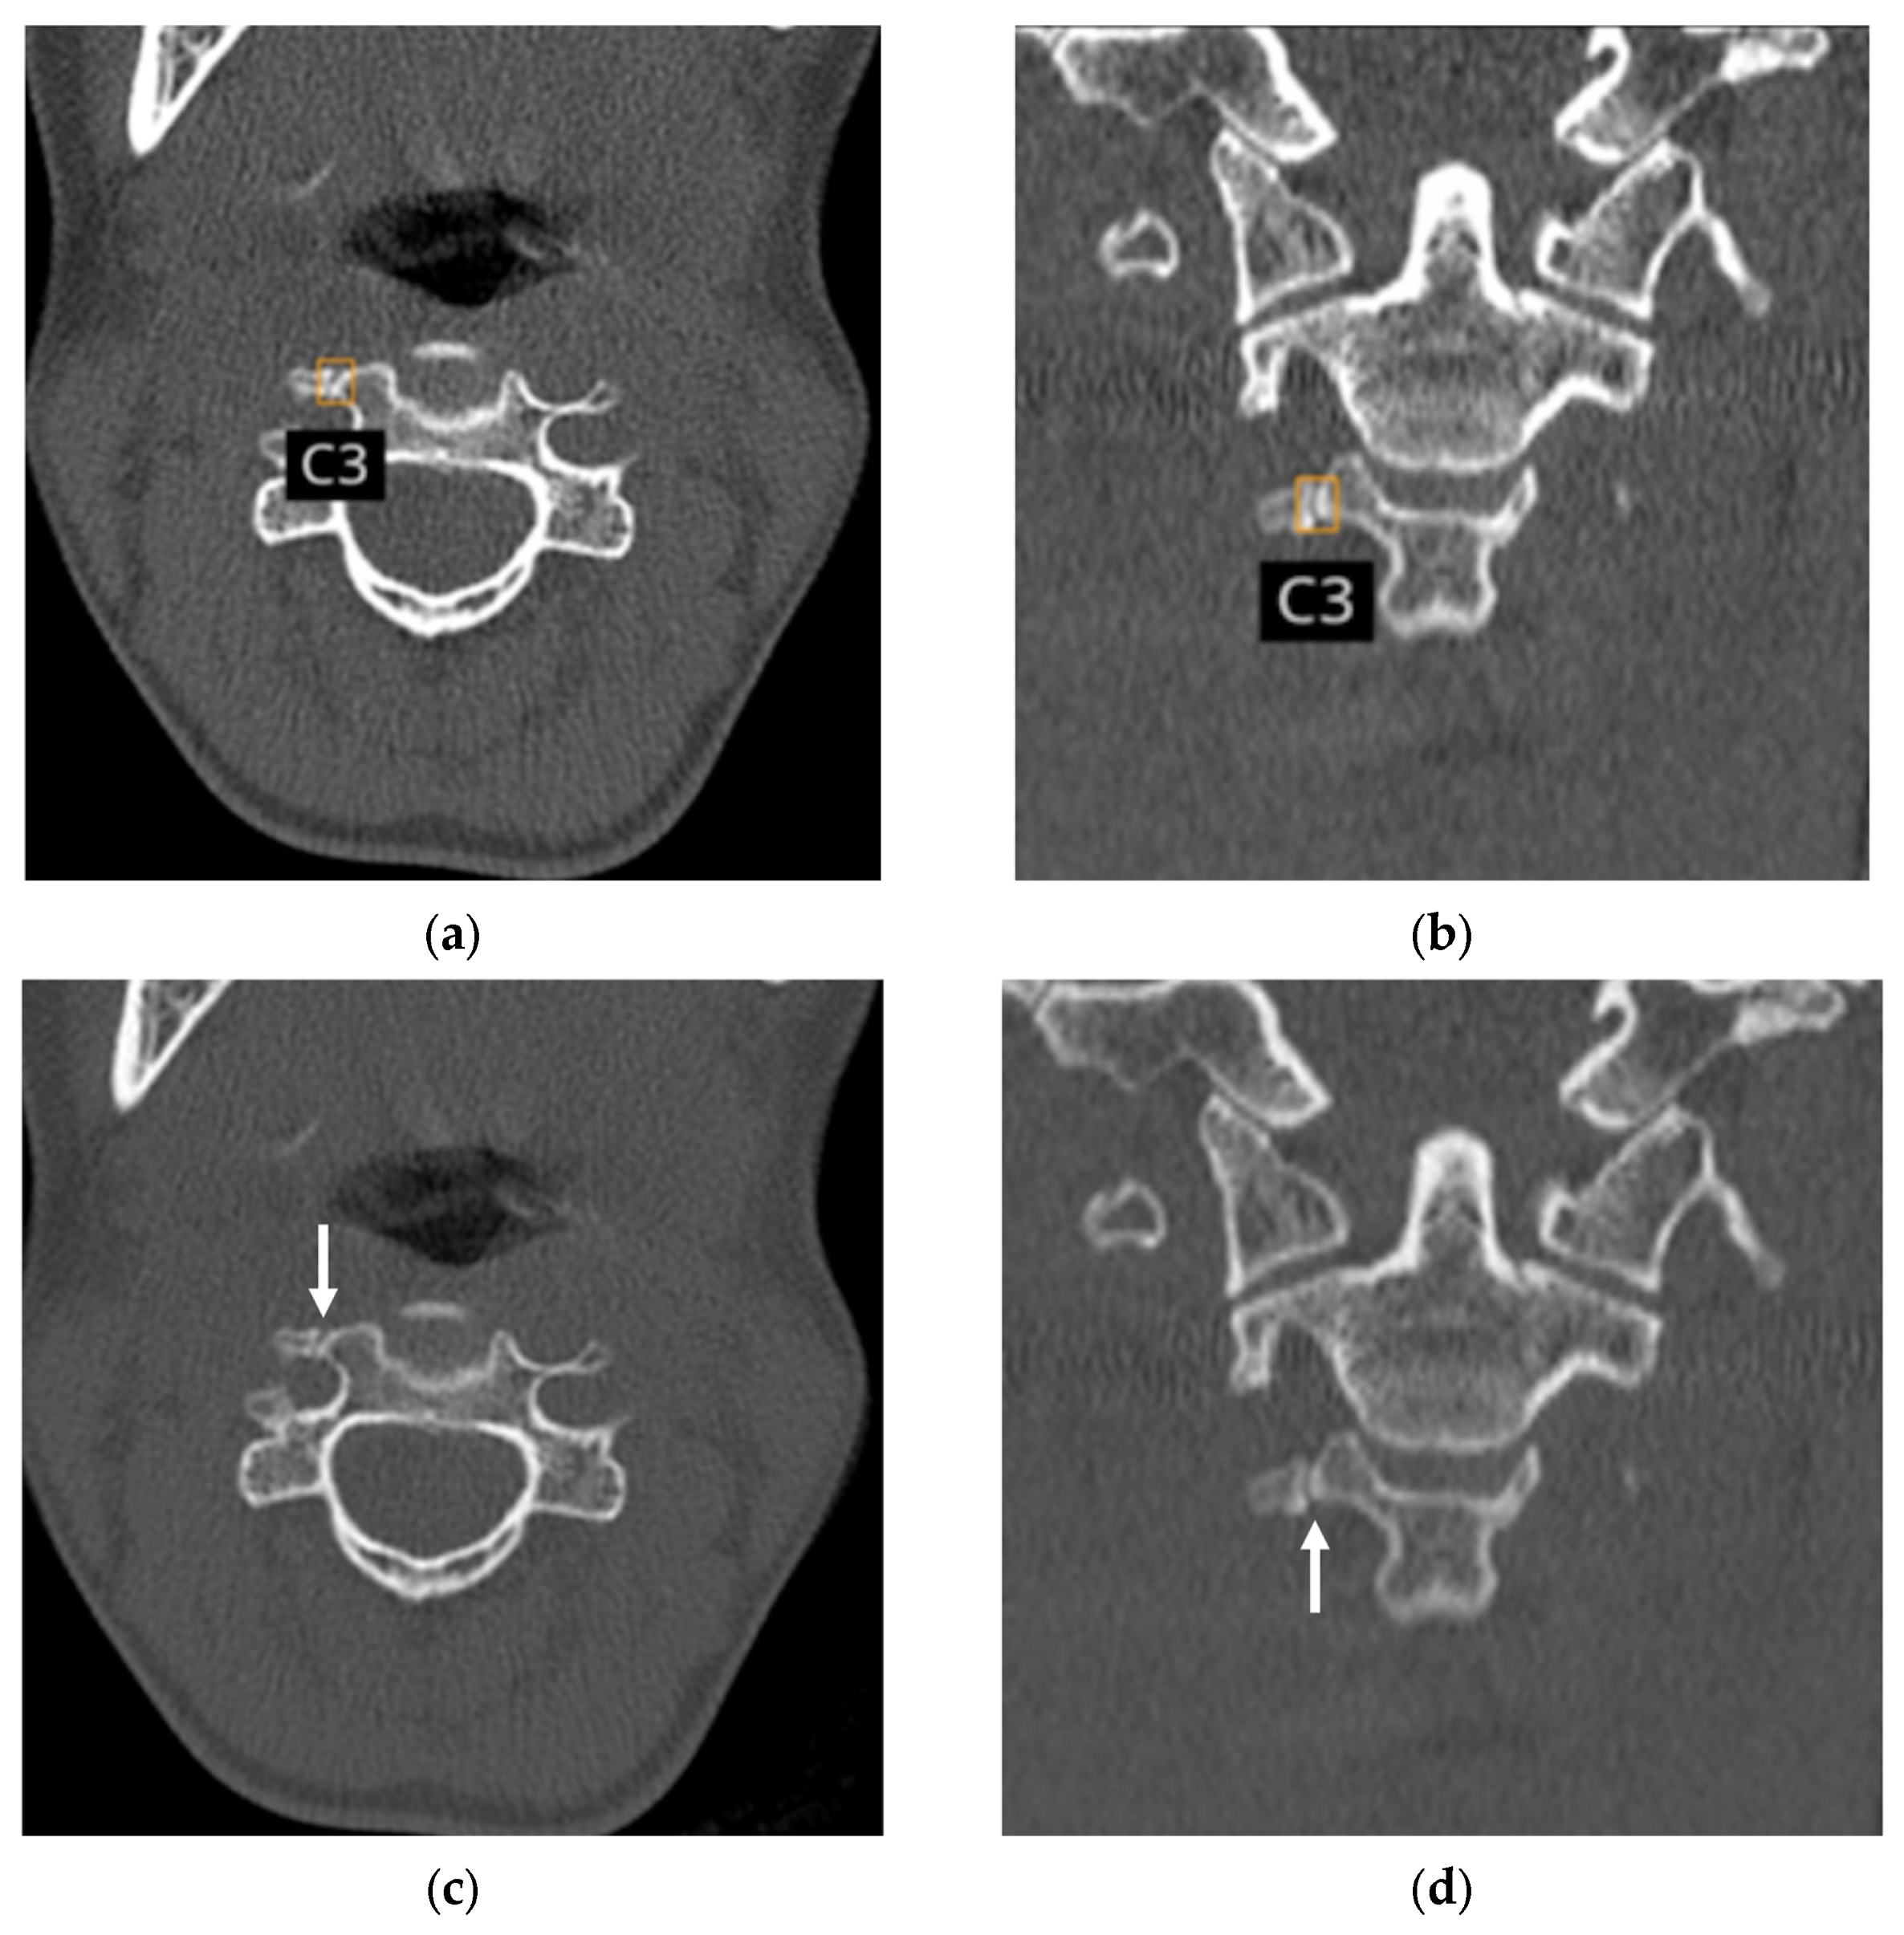

3.6. Analysis of False Positive and False Negative Cases